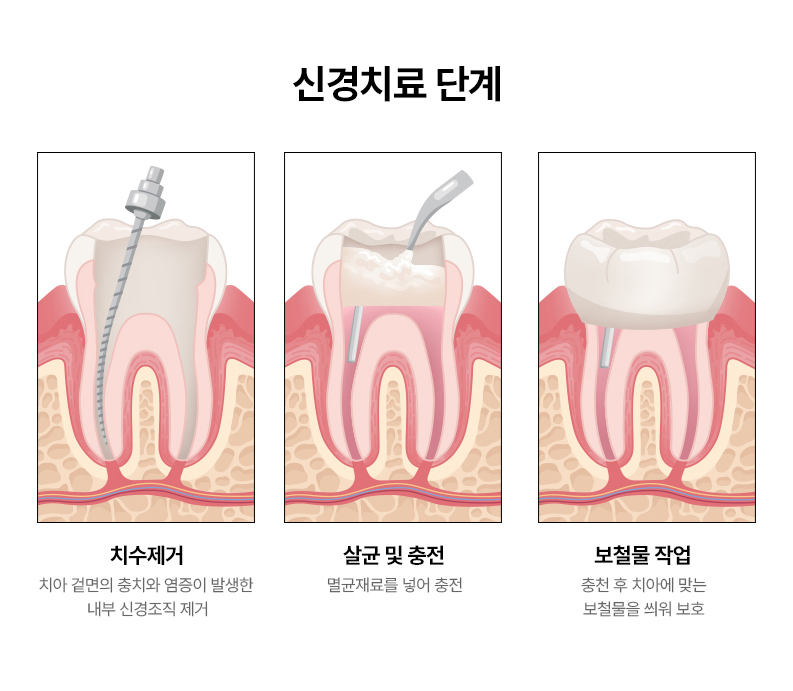

- 일반진료

-

자연치아 보존을 최우선으로 한

기본에 충실한 진료 - READ MORE